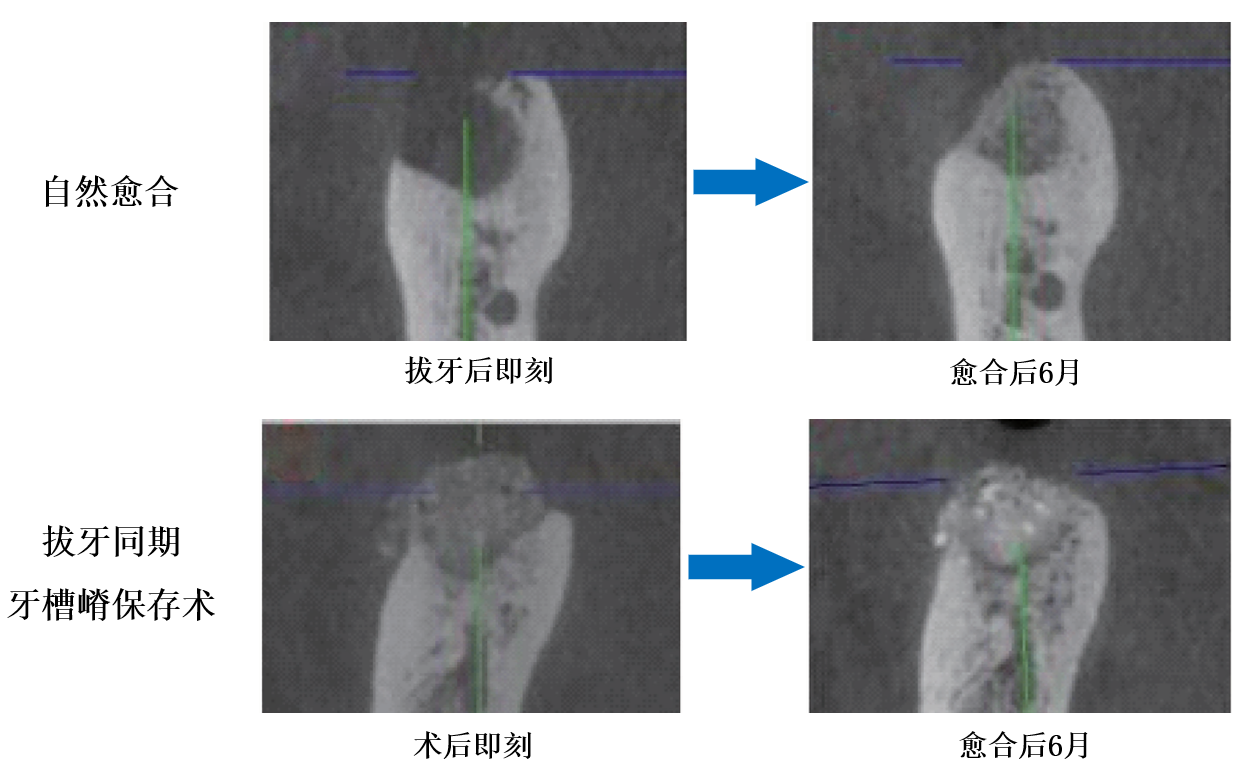

该课题组首先探索了重度牙周炎磨牙拔除后牙槽窝的愈合特征和改建规律,揭示此类患牙在拔牙前即存在不同程度的牙槽骨吸收,拔牙后自然愈合过程中有进一步的骨宽度和高度降低,造成缺牙区骨量不足,影响后续种植治疗。相关研究成果发表于国际口腔种植学权威期刊《临床口腔种植学研究杂志》(Clinical Oral Implants Research),其关键研究图片首次被选为杂志封面(2019年4月刊,DOI: 10.1111/clr.13418)。

上图:罹患重度牙周磨牙拔牙自然愈合后6月,拟行种植治疗位点牙槽嵴轮廓塌陷

下图:罹患重度牙周磨牙拔牙同期牙槽嵴保存术后6月,拟行种植治疗位点牙槽嵴轮廓丰满